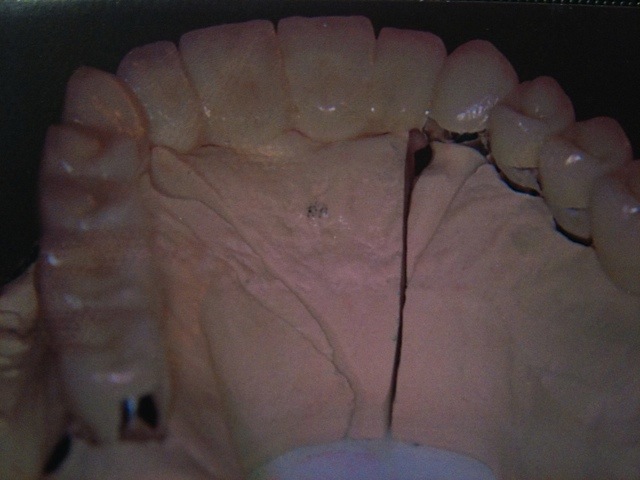

Die folgenden Patientenfälle sollen Ihnen einen Einblick in die Möglichkeiten der modernen Implantation geben.

Implantation – Patientenbeispiel 1: